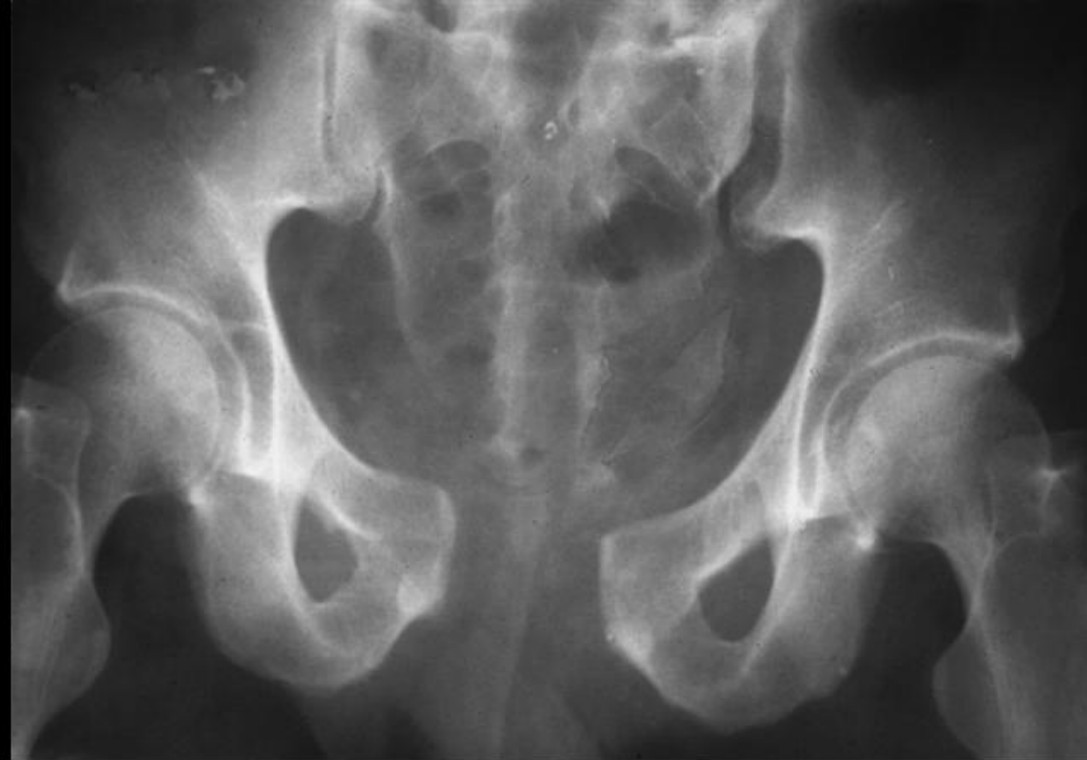

Pelvic crush injury

A 22-year-old Ubereats delivery man is brought in by retrieval to your tertiary ED having been run over by a …